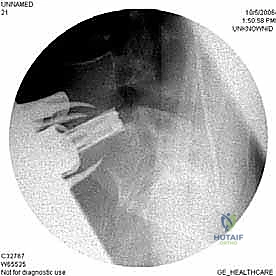

الخطوة 5: التثبيت (Fixation)

لضمان أقصى درجات الثبات والسماح للعظم بالاندماج بمرور الوقت، يتم تثبيت القفص باستخدام شريحة معدنية صغيرة ومسامير من التيتانيوم تُثبت في الأجسام الفقرية من الأمام. في بعض الحالات، قد يرى الدكتور هطيف ضرورة إضافة تثبيت خلفي بمسامير عبر الجلد (Percutaneous Pedicle Screws) لزيادة الدعم.